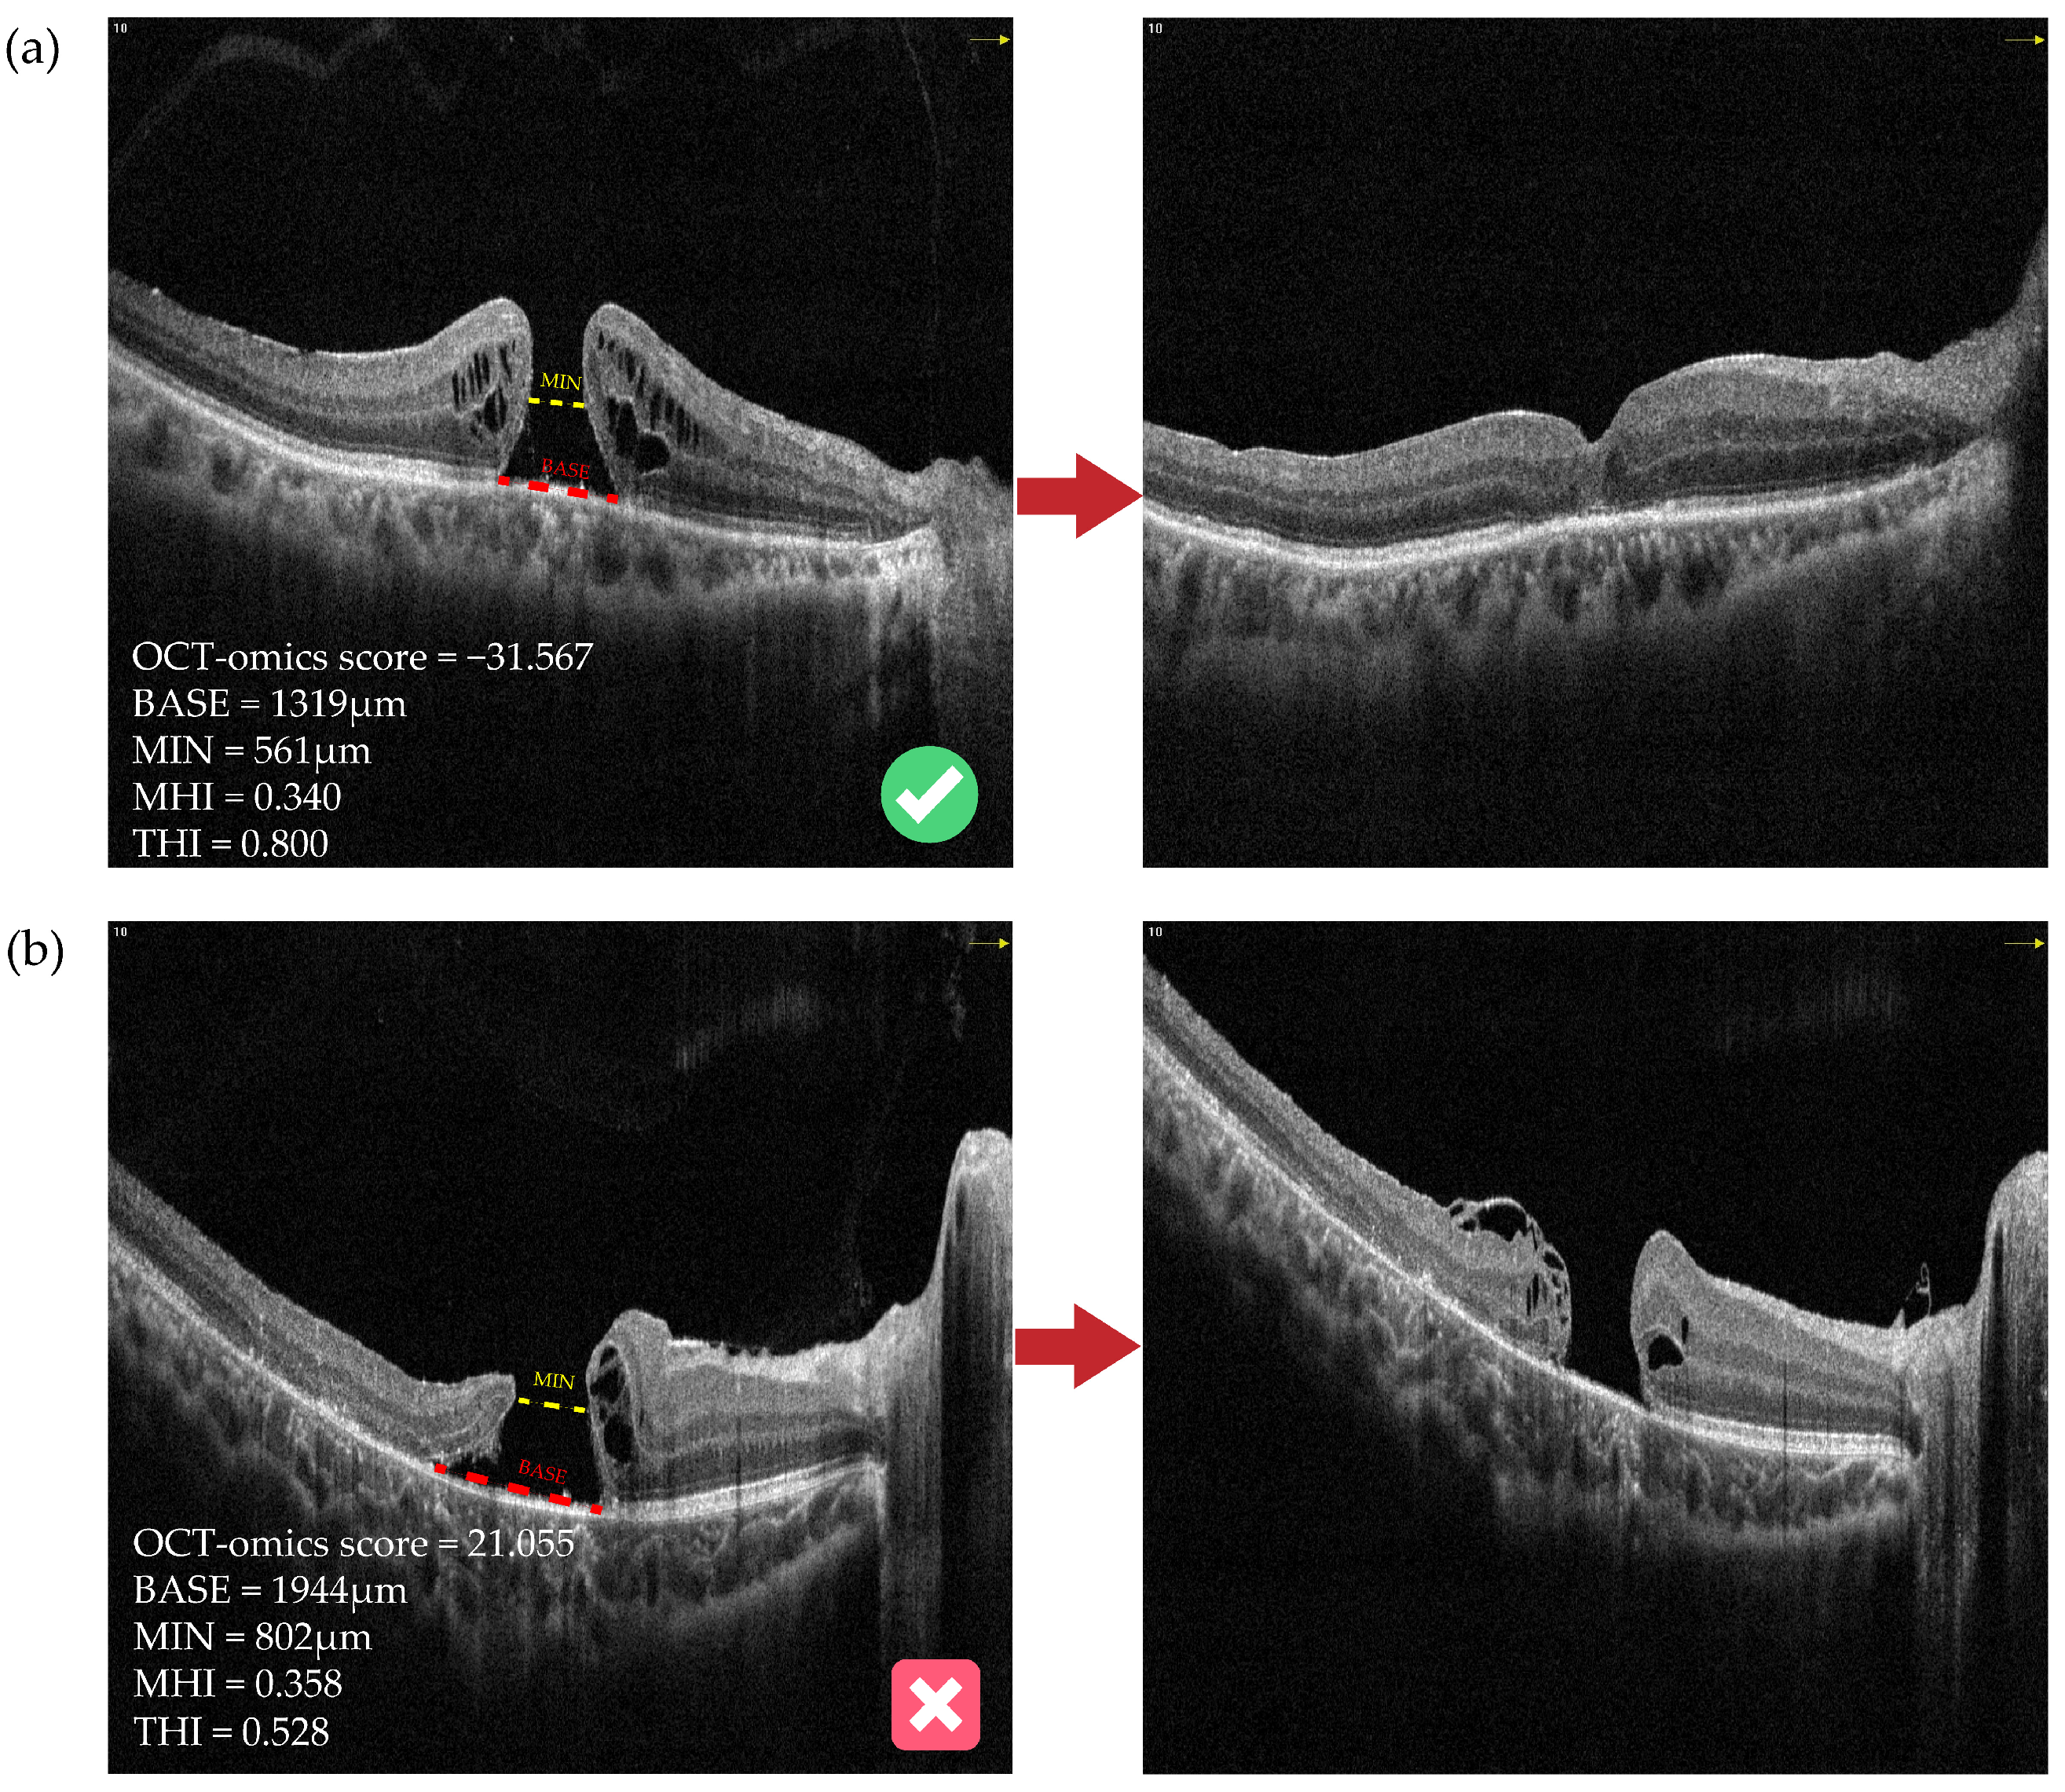

3.4. Clinical Implications of the OCT-Omics Model